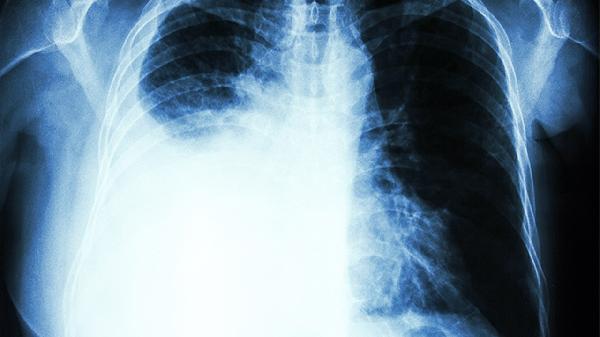

该药含杏仁、紫苏子等化痰降气成分,能够稀释呼吸道分泌物,促进痰液排出。对于慢性支气管炎急性发作时出现的痰鸣气喘、胸闷气促等症状,有助于改善气道通畅度。